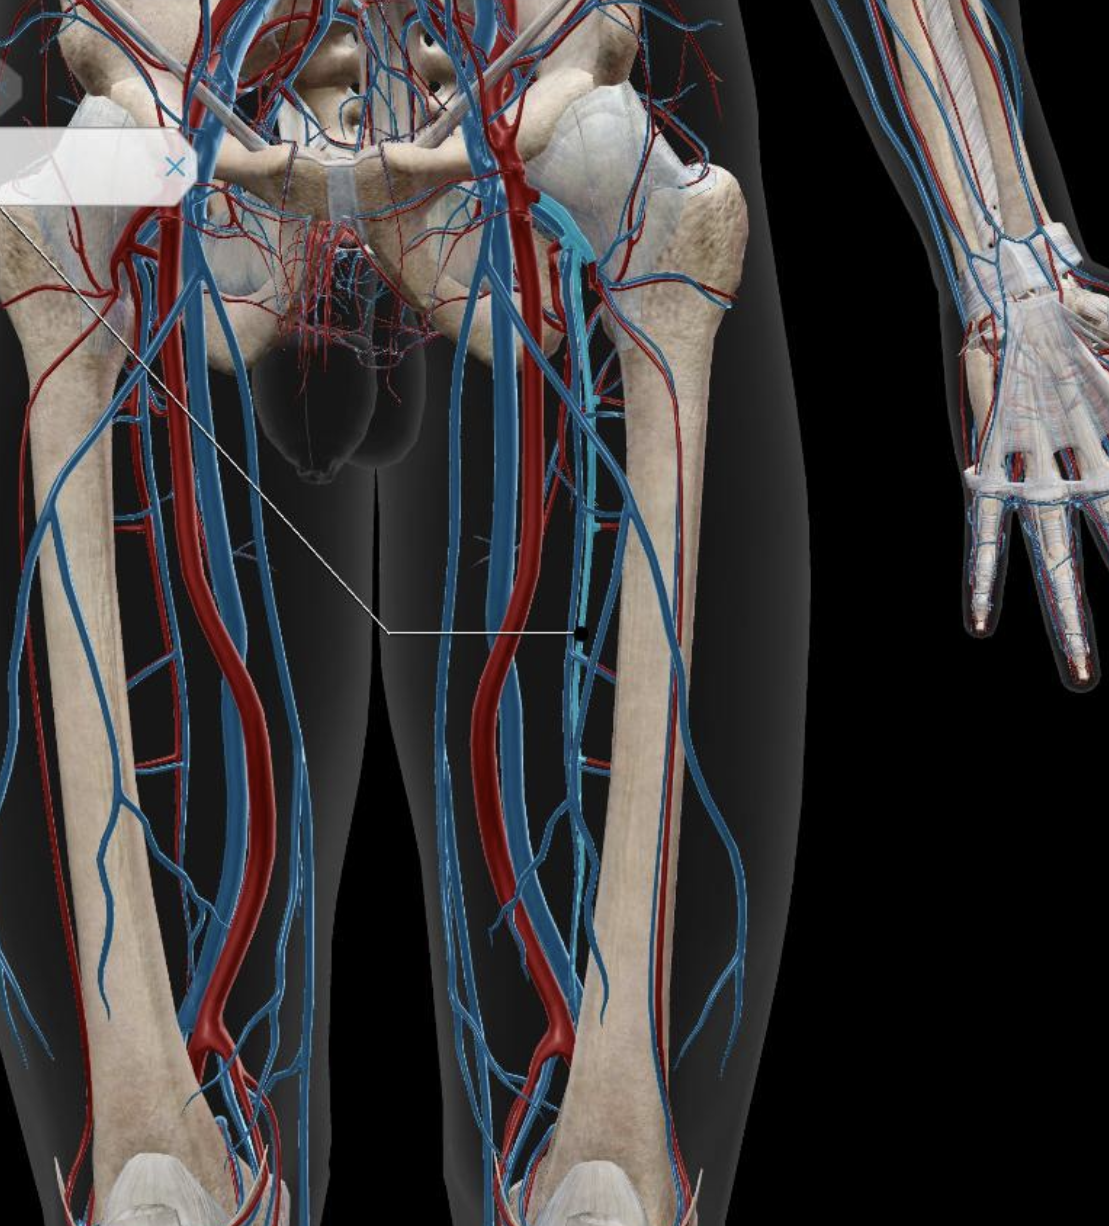

Femoral Artery

Common Iliac Artery

Internal Iliac Artery

Subclavian Artery

External Iliac Artery

Femoral Vein

Common Iliac Vein

External Iliac Vein

Internal Iliac Vein

Popliteal Vein

Great Saphenous Vein

Deep Femoral Artery